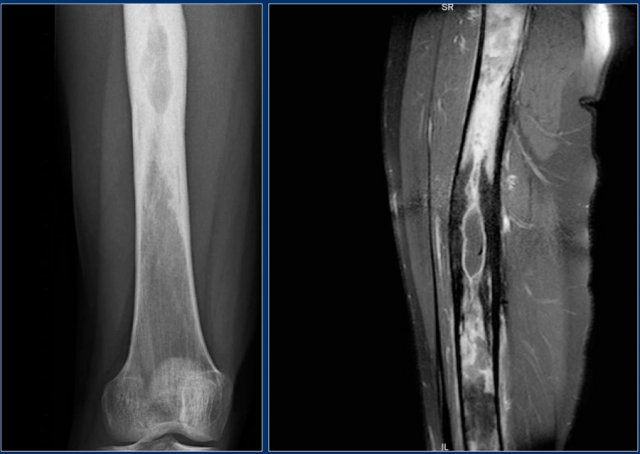

Here a NHL presenting as a non-specific ill-defined mixed osteolytic-sclerotic lesion in the proximal tibia.

Here a bone lesion in a patient with known NHL.

The imaging findings are non specific.